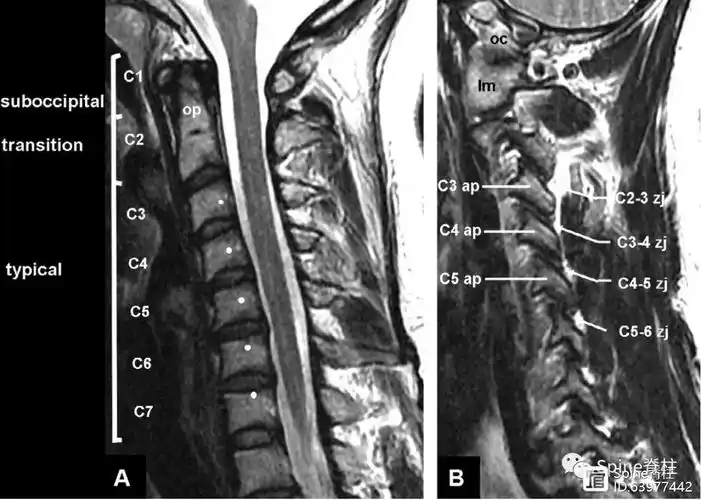

脊柱mri解剖图片

图示:矢壮位mri显示的颈椎结构和区域.白点:为上位椎屈伸运动中心.